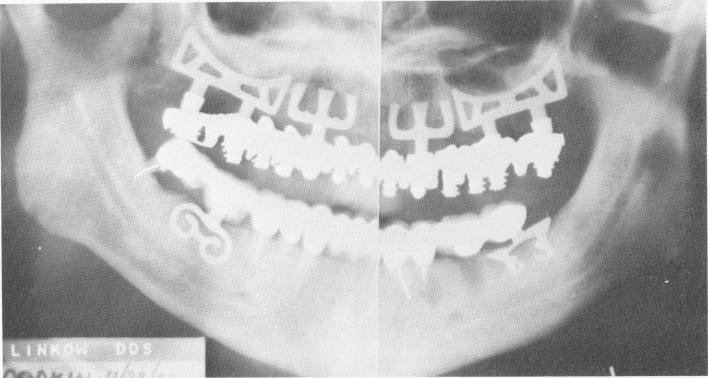

Fig. 11-158. The final Panorex. An apicoectomy had been done at the apex of the lower left first bicuspid tooth, and a tooth extraction was done 1 week before the radiograph was taken. (From Linkow, L. I.: Status of oral implants, 1969, Inform. Odontostomat., Vol. 1, 1969.)